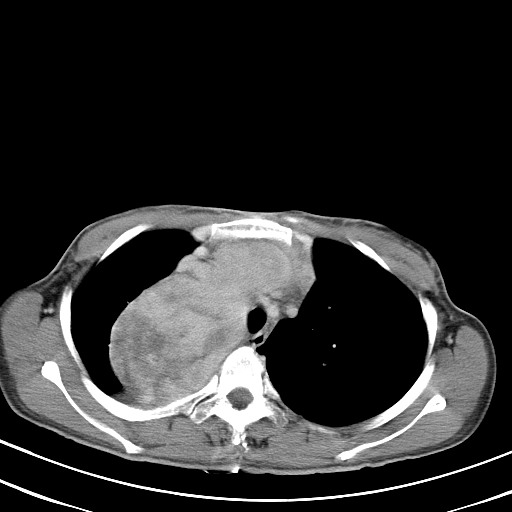

以下是引用汪涛同志在2007-8-2 0:40:00的发言:[br]病变虽然广泛,同时侵及双侧纵隔,但是无论左侧和右侧上下观察都是与右侧颈部甲状腺相延续的,而且强化幅度基本一致,又同时具有恶性病变病变的某些特征:肿块过大且密度不均,部分层面与正常纵隔结构分界不清,结合病史已有两年,考虑:胸内甲状腺肿恶变可能。[br]